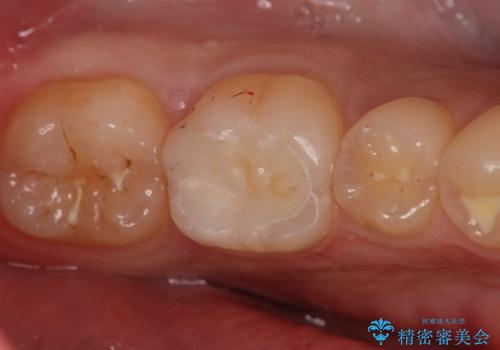

- 左下6番の治療のやり直しを希望し来院された患者様です。

保険の材料が劣化し段差や隙間ができてしまっている状態です。

自費の治療を希望されたため切削量・形態を考慮し、セラミックインレーでの治療を計画しました。

保険の材料と比較して、セラミックは劣化しにくく審美性も高い材料です。